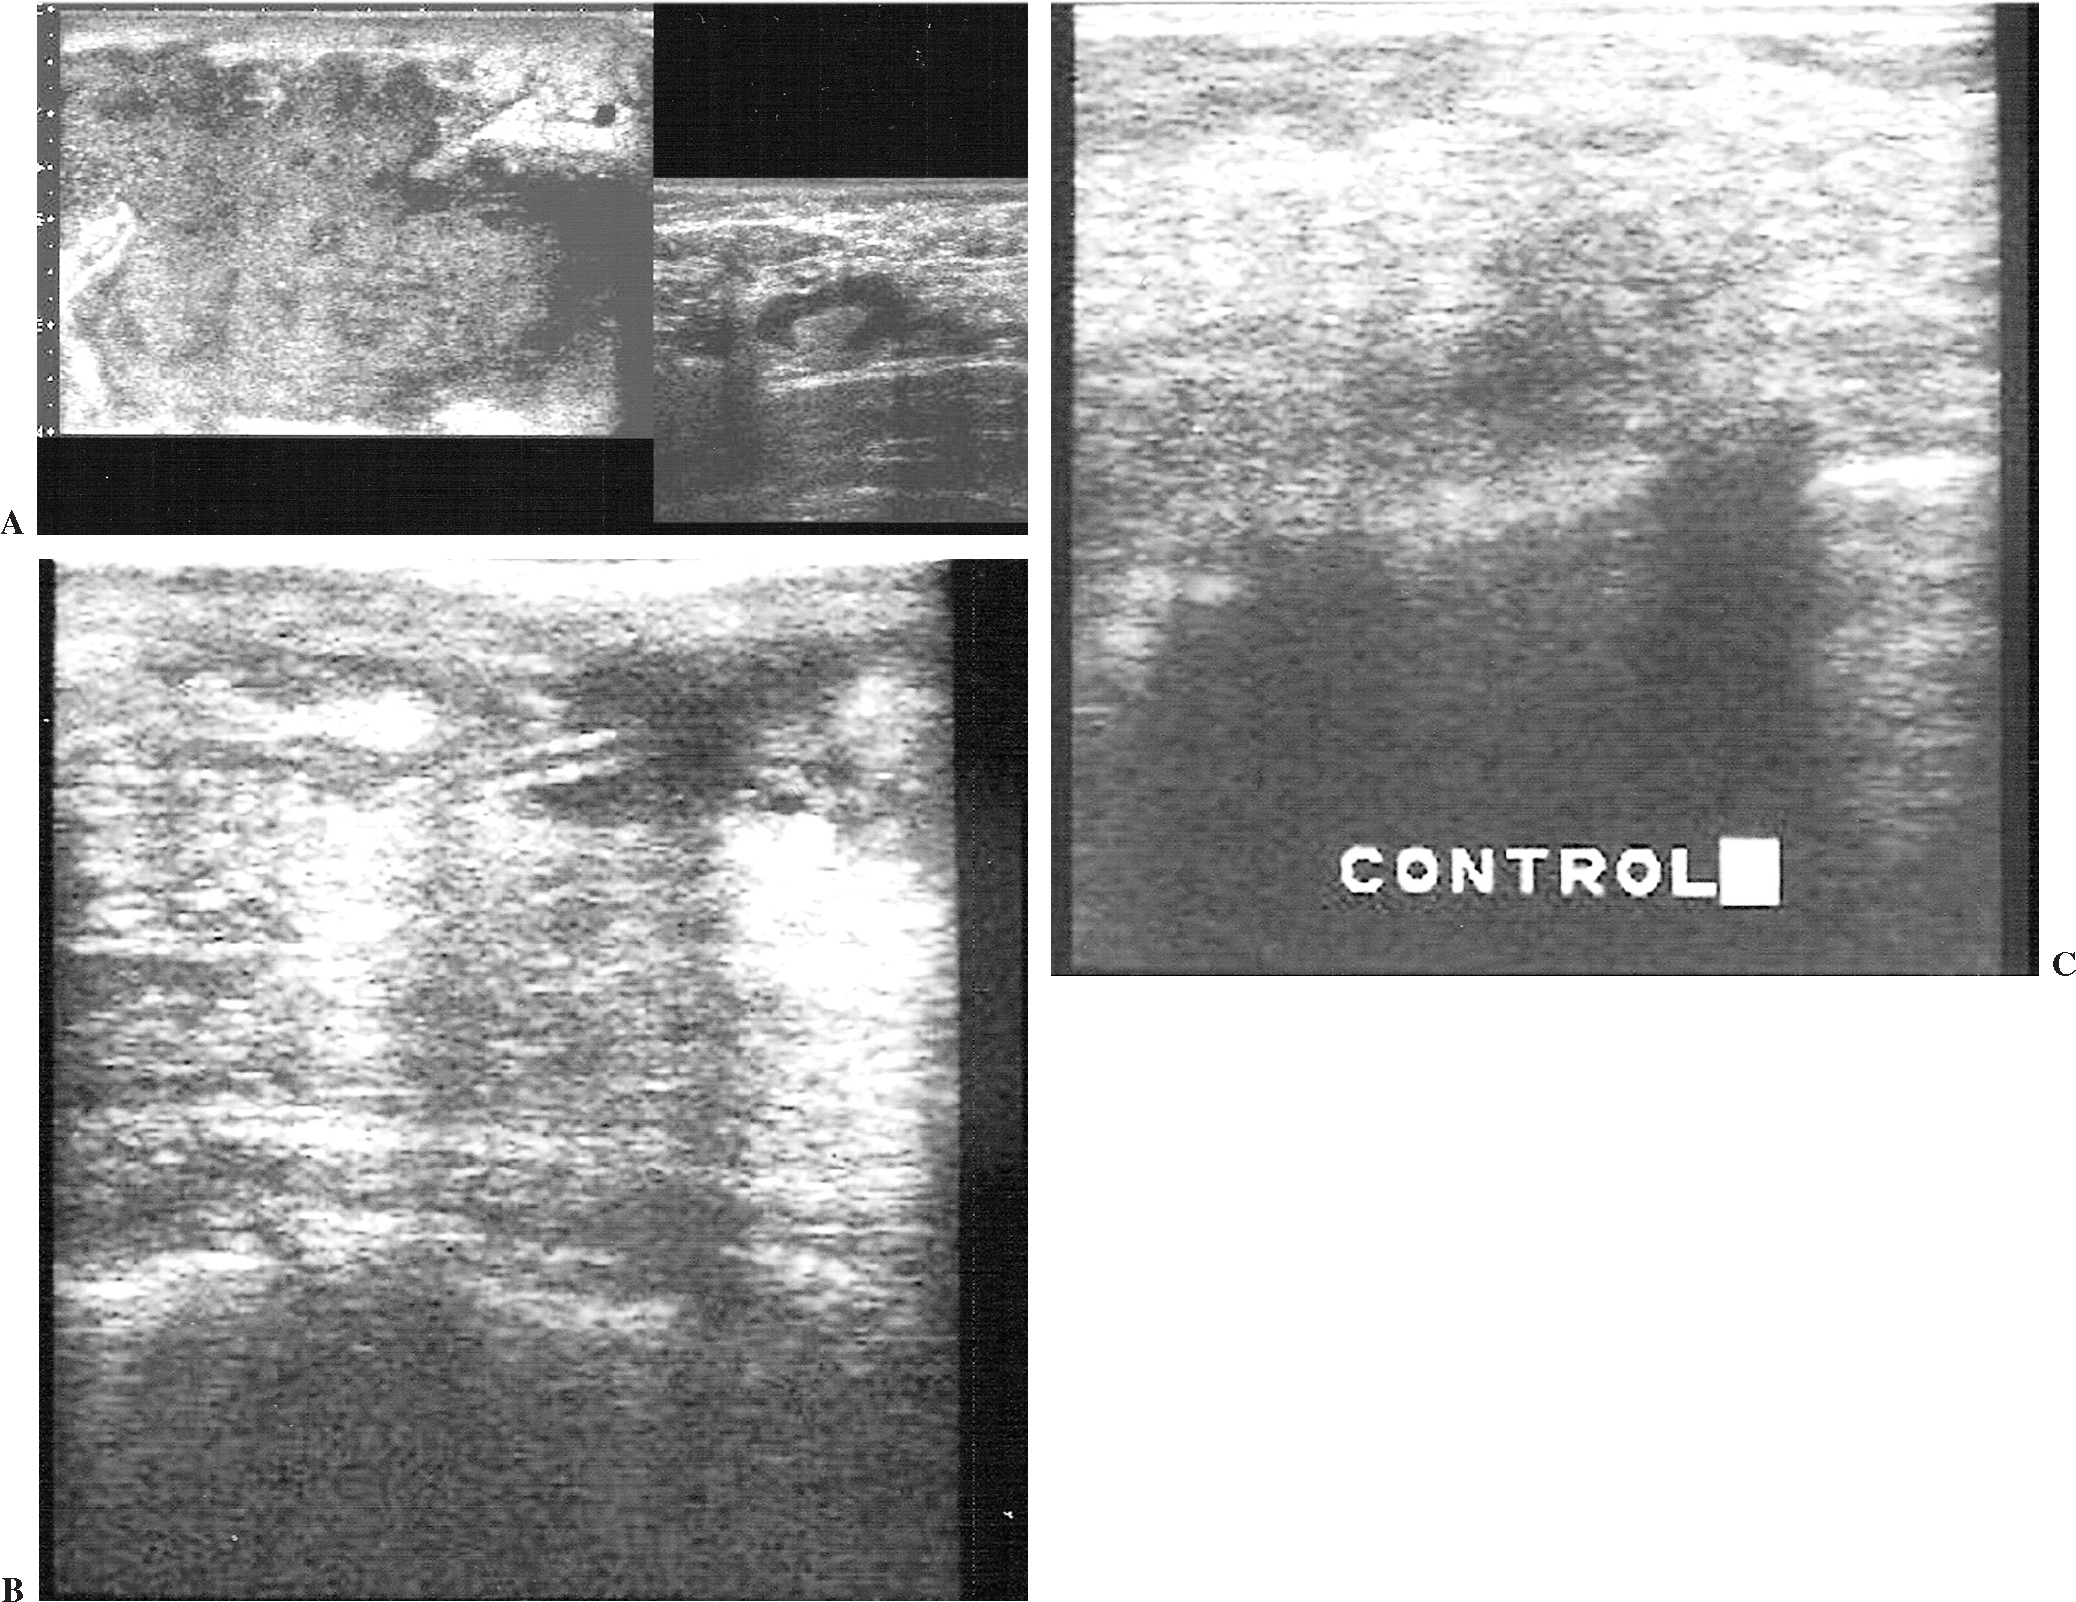

Realizamos el tratamiento de los abscesos menores de 3 cm con drenaje directo con PAAF guiado con ecografía, obteniendo siempre citología y cultivo (fig. 1). En caso de material muy viscoso se usó una cánula de plástico (2,0 mm). Después de drenado se realizaron seguimientos ecográficos en los 2-3 días siguientes hasta confirmar su resolución. Todo esto se combinó con tratamiento antibiótico y analgésico.

Fig. 1.--Absceso de mama. Ecografía mamaria. (A) Nódulo oval hipoecoico y homogéneo de pared gruesa y menor de 3 cm. (B) Drenaje del absceso con aguja fina. (C) Control posterior a drenaje.

Los abscesos mayores de 3 cm, siempre y cuando no fueran multitabicados, se drenaron mediante catéter pig-tail 6F con anestesia local, abriendo una pequeña incisión en la piel para facilitar la punción (fig. 2). Después se procedió al lavado con suero salino.

Fig. 2.--Absceso de mama. Ecografía mamaria. (A) Colección ecogénica, irregular con margen lobulado e inhomogénea mayor de 3 cm, con adenopatías axilares acompañantes. (B) Drenaje con catéter pig-tail. (C) Control en 7 días.

En contraposición a esto, y basándonos en la experiencia de otros autores9-11, decidimos realizar el tratamiento de los abscesos menores de 3 cm con drenaje directo con PAAF guiado con ecografía, realizando siempre citología y cultivo (fig. 1). Después de drenado se realizan seguimientos ecográficos en los 2-3 días siguientes hasta confirmar su resolución. Todo esto se combina con tratamiento antibiótico y analgésico. Los abscesos mayores de 3 cm, siempre y cuando no fueran multitabicados, se drenaron mediante catéter pig-tail 6F (fig. 2). Aplicando estas medidas la evolución clínica fue satisfactoria en todos los casos, y el resultado estético mejor que con el drenaje quirúrgico, aspecto ya demostrado en la literatura5,12,13.